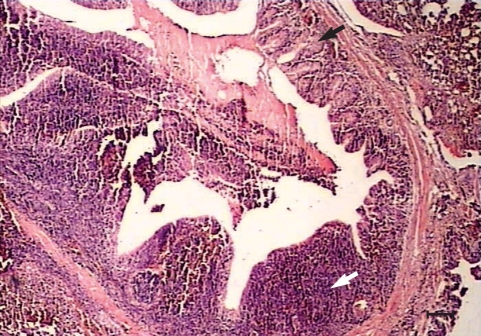

Histopathological changes were observed in organs of all the experimentally infected chickens at day 240 PI. Peribronchiolitis with infiltration of lymphocytes, and hyperplasia of bronchiolar associated lymphatic tissues (BALT) and goblet cells, were evident in the lungs of infected chickens (Fig. 1). Mild hemorrhages, lymphocytic infiltrations, and a few eosinophils were observed in the meninges, especially over the cerebellum (Fig. 2). Perivascular infiltration was seen around some of the vessels in the cerebral parenchyma in most of the infected chickens. Mild focal infiltration of lymphocytes was present between cardiac muscle fibers of the infected chickens. No lesions were seen in other tissues of the infected chickens. No abnormality was observed at gross and histological levels in the liver, lungs, kidneys, heart, brain, and other tissues examined of uninfected control chickens.

Pathological findings in the lungs of the infected chickens were new and different from the previous short term observation [1]. Hyperplasia of BALT and goblet cells shows the defense mechanism to the chronic infection. The brain lesion was not described in the previous experiment. Since there was only a mild lesion in the brain, there was no behavioral change of the infected chickens. In the present study, no larvae were detected during the chronic phase in the liver, lungs, kidneys, or skeletal muscles in either larval recovery or histological studies. However, larvae were recovered from the brain of 3 infected chickens by the squash method.